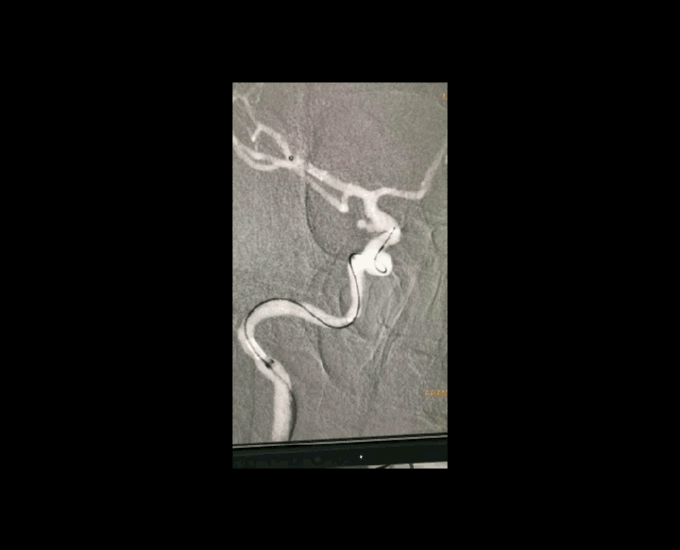

大C塑形

10mm以上的大动脉瘤:

(1)C型头端完全进入动脉瘤囊内,微导管的盘旋有利于均匀填塞

(2)避免微导管头端过早踢出

病例一